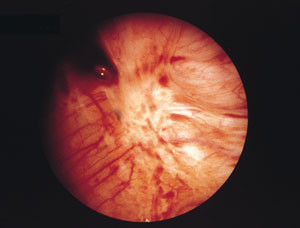

Endometrios är en kronisk sjukdom som drabbar 5 – 10 procent av kvinnor i reproduktiv ålder och förorsakar i många fall mycket svåra smärtor och reducerad livskvalitet. Ett centralt fenomen i sjukdomens patofysiologi är förmodligen implantation och inväxt på ektopiska ställen av avstötta endometrieceller, vilka initialt ger upphov till en lokal inflammation (fig 1). Möjligheten för endometriefragment att implantera tycks bero på att de lymfocyter, s k NK-celler (natural killer cells), som normalt känner igen och bryter ner bl a endometrieceller (liksom t ex virusinfekterade celler och tumörceller) utan föregående sensitisering, hos vissa kvinnor har en defekt cytotoxicitet (1).

I den kaskad av inflammatoriska processer som initieras i samband med adhesionen och implantationen frisätts olika substanser av vilka en del är smärtframkallande. Denna process initieras varje gång bäckenhålan exponeras för en retrograd menstruation. Frekventa, rikliga och/eller långdragna menstruationer har visat sig vara relaterade till förekomsten av endometrios, men å andra sidan har tidigare användning av p-piller, som minskar blödningsvolymen, eller IUD (intra-uterine device), som kan öka densamma, inte visat sig vara specifikt relaterade till förekomst av endometrios (2). Det annorlunda kontraktionsmönstret i myometriet med hyperperistaltik, som påvisats hos kvinnor med endometrios (3) bidrar sannolikt genom att öka volymen av retrograd blödning. Symtomet under denna fas av sjukdomen är huvudsakligen menstruationsrelaterad bäckensmärta. Så småningom övergår den akuta inflammationen i en kronisk form med fibrosbildning runt och in i härdarna (fig 2). När endometrioshärden inkapslats i fibros blir produktionen och expositionen av inflammationsmedierande substanser begränsad. Samtidigt som vissa härdar fibrosomvandlas uppstår dock nya härdar. På så sätt tycks såväl akut som kronisk inflammation pågå parallellt i lilla bäckenet hos många kvinnor. Endometriosvävnaden har en potential att växa in i omgivningen (fig 3), och denna invasiva växt, liksom fibrosen, kan involvera afferenta nerver, vilket resulterar i mer eller mindre kronisk smärta.